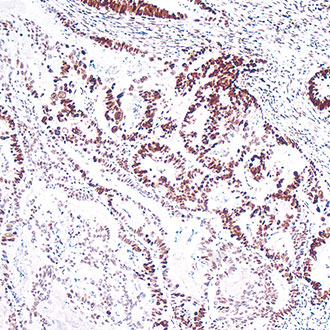

IHC

免疫组织化学(IHC)